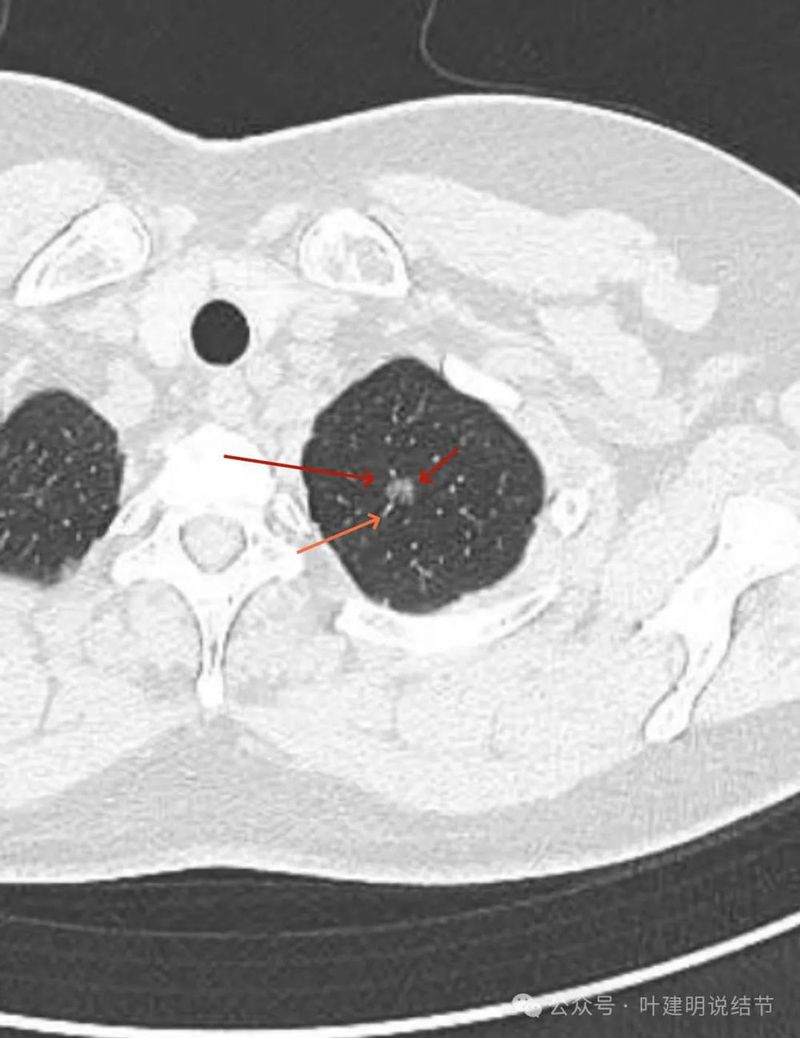

病灶出现 ,位于左肺尖,表面不平,中间有小空泡征,边缘欠光滑,灶内密度也欠均匀,整体轮廓与边界却较为清楚。

灶内细支气管扩张,边缘有小血管进入,表面不平有小棘突或毛刺,灶内密度不均,有点状高密度。